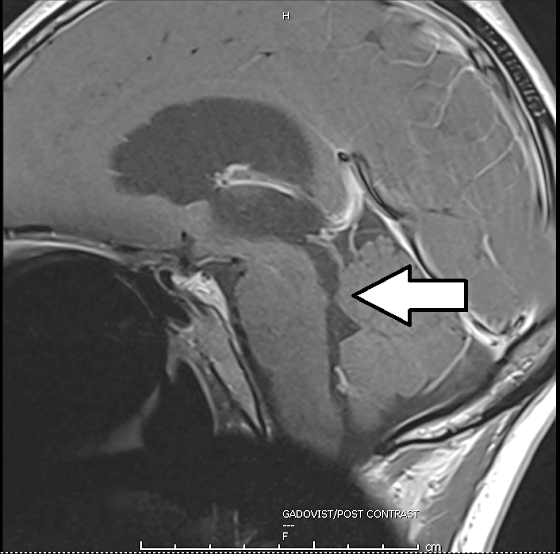

脑干和小脑之间的下水道狭窄,脑脊髓液的循环受阻(箭头处)。

以磁力共振扫描作进一步诊断时,我发现龙妈妈的脑干和小脑之间的下水道狭窄,的循环受阻,造成慢性脑积水,导致脑压升高,引发视神经水肿、眩晕等症状。